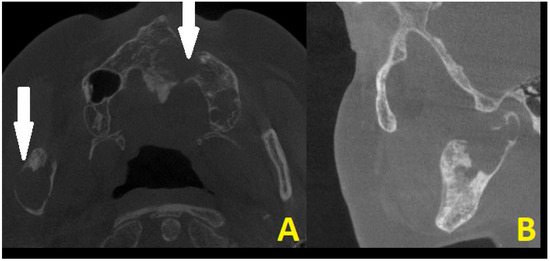

Figure 4. The surgical double approach consisted of the preauricular approach and the submandibular approach. The nasotracheal tube was sutured to the nasal septum and then retruded distally as per the tube placement algorithm [6]. A layer-by-layer preparation granted a good surgical view of the operated field with good protection of the facial nerve fibres. The TMJ standard prosthesis used was the Medartis 2.0 Modus System (Basel, Switzerland—right condylar head prosthesis (Titanium ASTM F67) with a carrier element, 2.0 mm four connecting screws screwed together with Medartis Reco plate 2.5, 2.5 mm connecting screws for proper mandibular vertical ramus height reconstruction, a stable position on the healthy part of the right mandibular ramus, and an angle free of OKC lesion. The pterygoid muscles were healthy and were sutured back to their initial position, in this case towards the titanium condylar head. The main lesion was located in the mandibular bone and had some cortical spread in the joint area. The articular disc and part of the capsule were healthy and not involved in the lesion, and because of that, fat grafting was not necessary. Any additional iliac crest bone grafting or fat was also not necessary. An additional four IMF (intermaxillary fixation) screws (Medartis, Basel, Switzerland), 2.0 system speed-tip 8/11 mm long, were used with elastic fixation. During the postoperative period, the patient was scheduled to use elastic rubbers on the IMF screws to stabilize the occlusion and surgery results. Currently, a custom-made individual TMJ prosthesis seems to be a good gold standard of treatment, especially in cases involving condylar disc damage, disruptions along the condylar fossa, and total joint resection. In some cases, such an approach with a standard, not custom patient-made, individual TMJ endoprosthesis solution is also quite effective, with fewer costs, good functional results, easy placement, no need for further glenoid fossa preparation, and the presence of just one metal alloy, the titanium. In this instance, the overall surgery outcome was very good, and the patient was satisfied with the results and the decreased necessity for any more advanced and costly procedures.